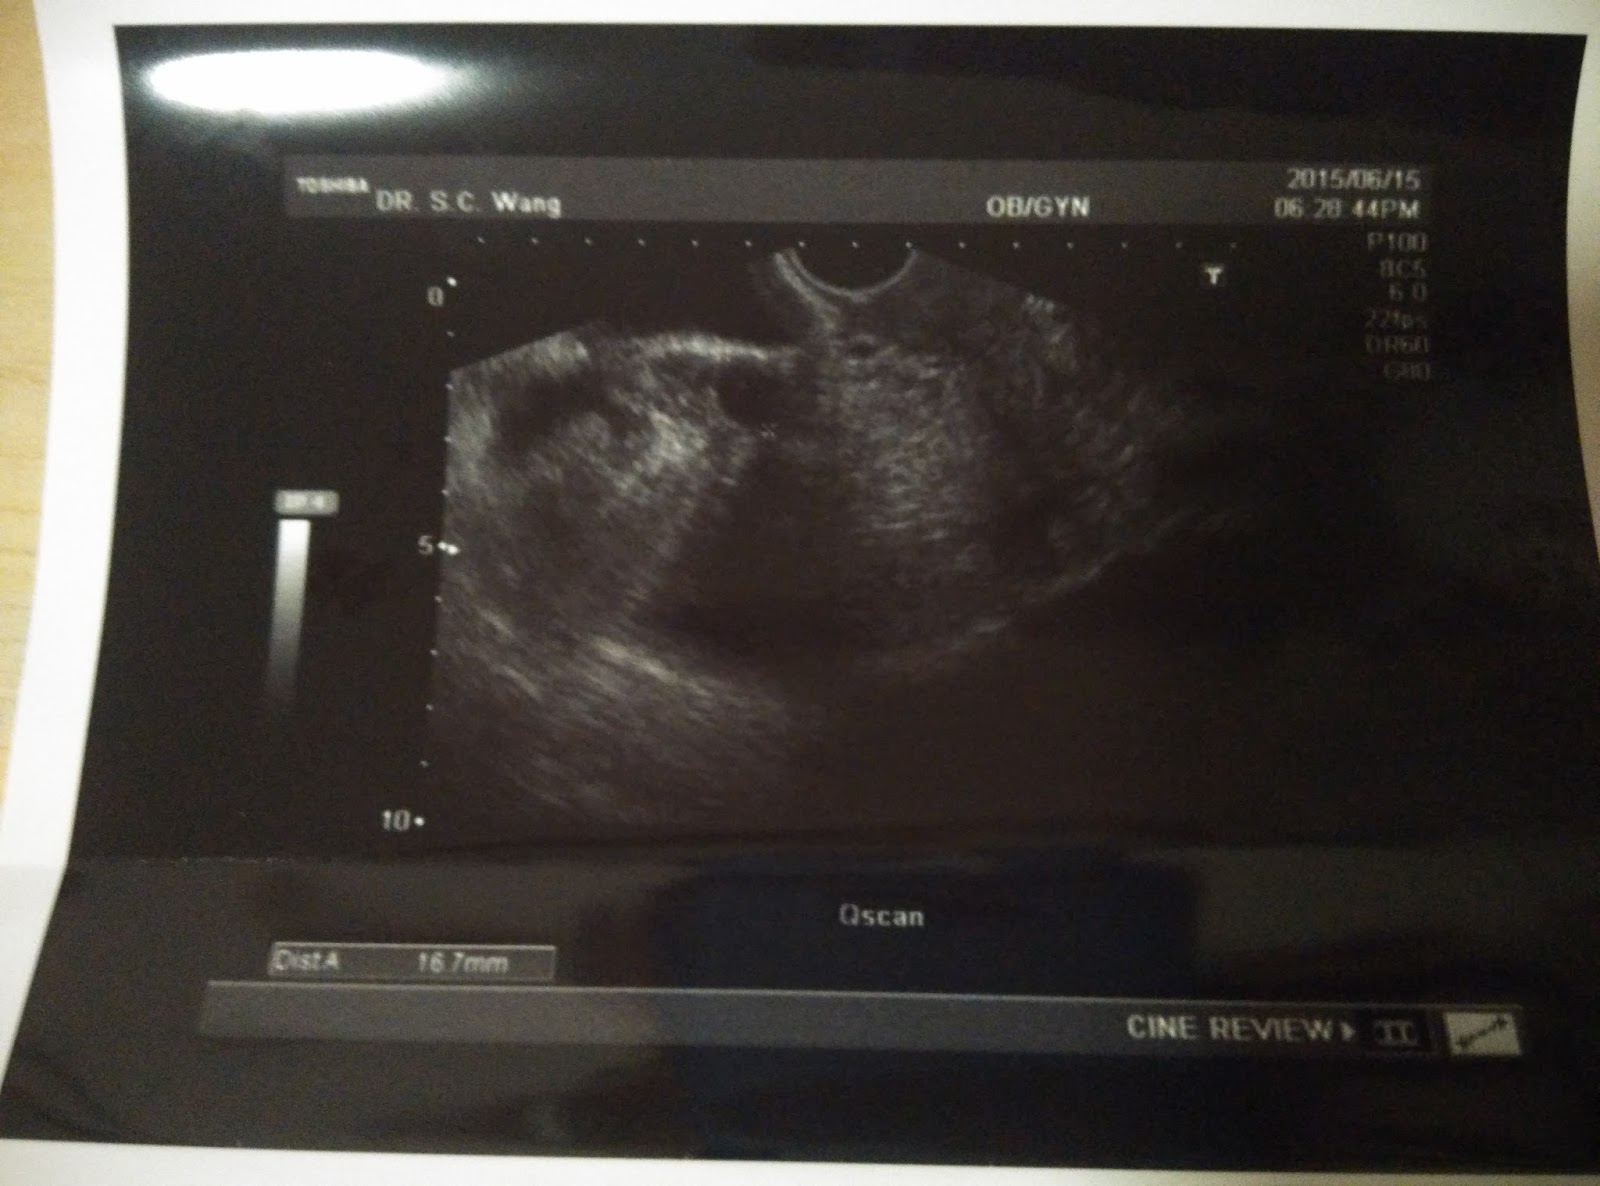

今天是我週期的第十二天,也是的要回黃醫生那邊覆診的日子。

這次去看醫生,主是想看看有沒有優勢卵泡。

之後醫生便馬上為我進行超聲波檢查。

我十分緊張,急不及待的問醫生有沒有比較大的卵泡。

醫生說有一粒成熟的,其餘的也是十分細小的。

我有多囊卵巢,所以這也是很正常的事。

其實只要有一個成熟的卵泡,我已心滿意足了。

我最大的那個卵泡在右方,直徑為1.67cm。

而左邊最大的卵泡,就只有1.23cm。

其實,如果只計卵泡,用了12天便有1.67,我已經很滿意了。

可惜內膜卻很薄,只有5mm,根本不適宜植入。

不過厚度已比上個月有進步了。

所以醫生開了E2給我服用,

用來養卵及內膜。